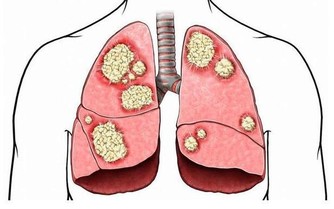

最後才是含脂肪的食物,包括肉、蛋、奶在內,這一部分佔10%左右。肉吃得過多易生濕熱,比如潰瘍性結腸炎就與飲食不節、情志內傷及濕熱、陽虛體質有關。